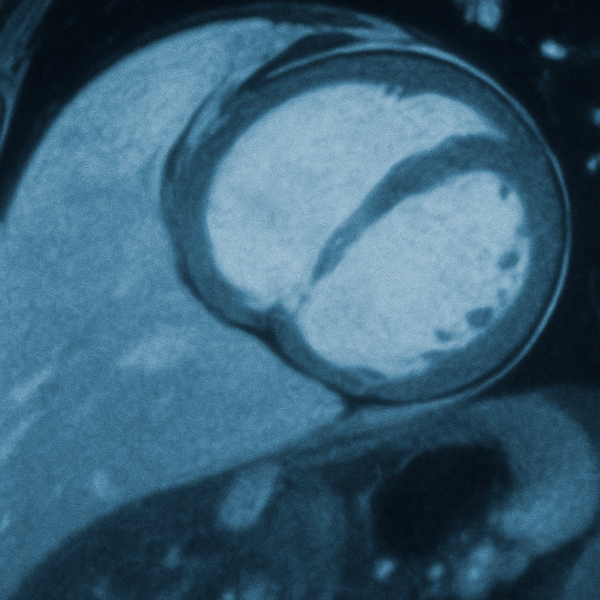

1st Cardiac MRI course Dubai, 22-24 Nov 2025